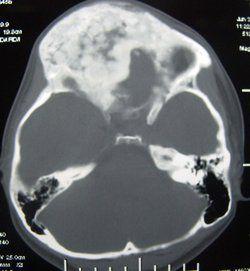

CT及MRI檢查

CT檢查費用雖較X線照片高,但其密度分辨高於X線、對病骨內的囊變、破壞、鈣化和骨化顯示較X平片敏感準確。CT橫斷面克服了常規X平片前後重疊的缺點,可用於頭顱、脊柱和骨盆等重疊較多的部位。 MRI對MAS的病理顯示無疑較常規X線或CT更敏感,能顯示大部分在X線平片或CT片上不能顯示的病灶(如壞死、液化、出血),纖維或纖維骨樣組織病灶在T1加權像和T2加權像均呈低信號。骨幹結構不良在病變的不同階段可有不同的病理改變。如病灶內的壞死液化在T1加權像上呈低信號,在T2加權像上呈高信號。

如壞死組織合併出血,T1加權像上呈高信號。病灶內的鈣化和周緣的硬化在T1加權像和T2加權像上呈明顯的低信號。

此外,少數病灶邊緣在T1和T2加權像上呈薄帶狀環狀高信號,其病理機制不清。某些病灶在T1加權像上呈不均勻的中低信號,而在T2加權像上則平片所見的“絲瓜筋”樣纖維結構不良。而液化的病灶在T1加僅像上為中低信號,在T2加權像上為均勻高信號。